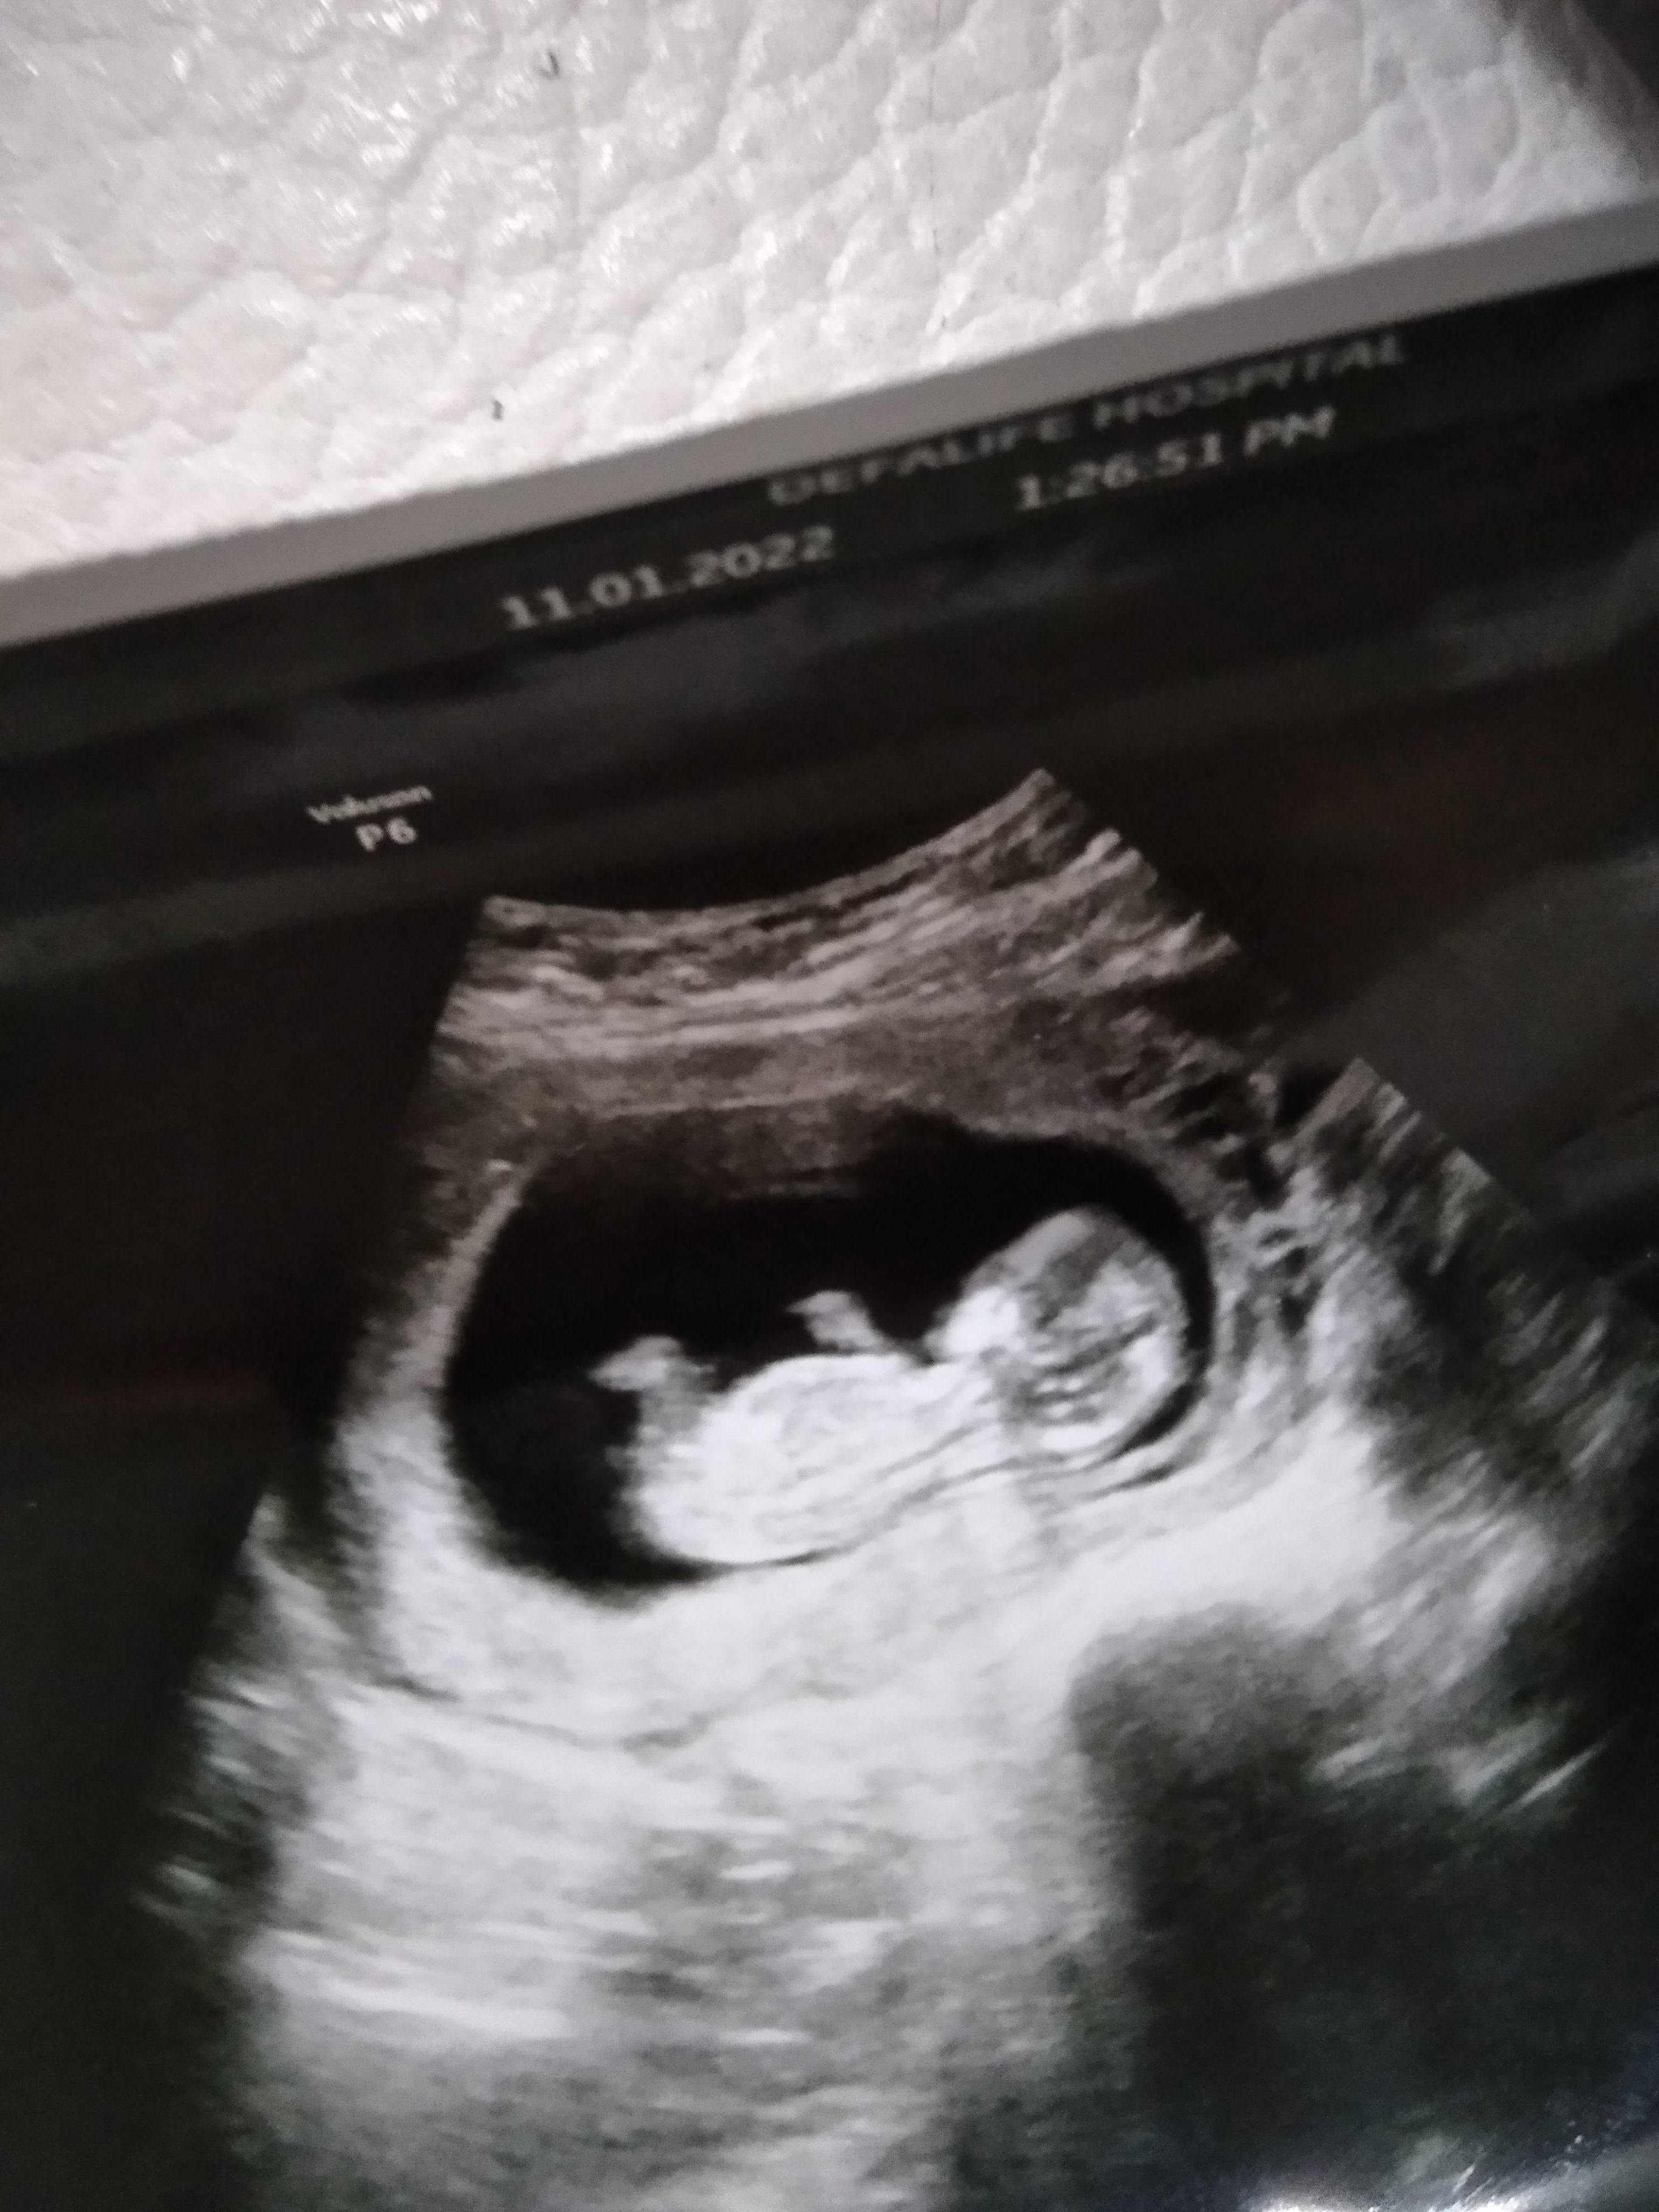

Merhaba lar bebeğimin 12 haftalık ultrason görüntüsü cinsiyet tahmini yaparmisnz

Ekli dosyalar

• IMG-20220518-WA0041.jpeg

IMG-20220518-WA0041.jpeg

704,8 KB · Görüntüleme: 245